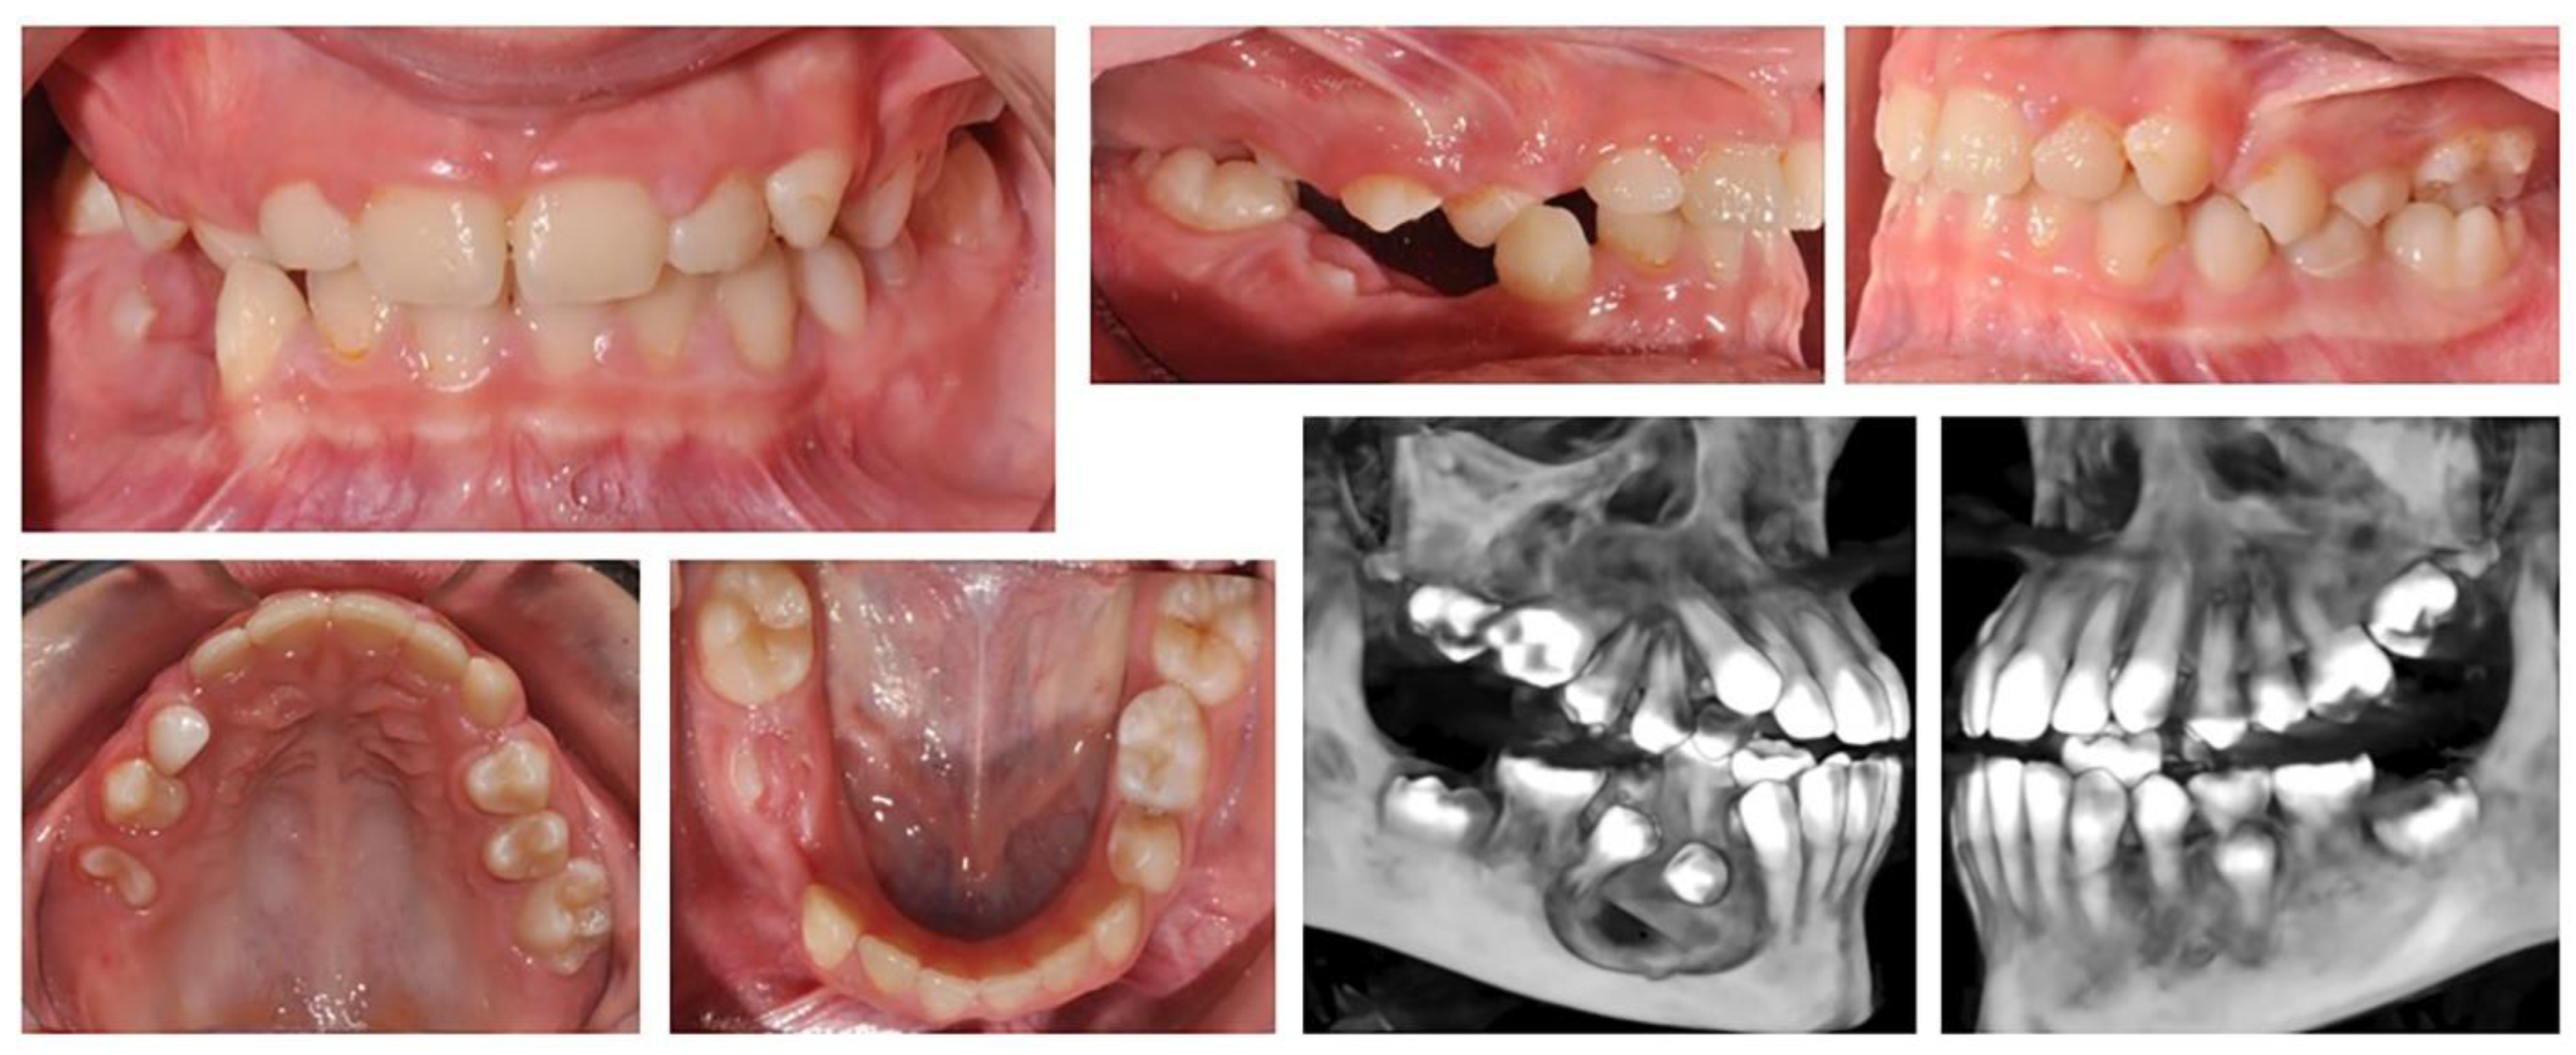

2.2.2. We present a 10-year-old girl aimed for the orthodontic treatment by Maxillofacial surgeon. A cystic lesion involving teeth 44 and 45 was detected, which was operated on and tooth 44 was extracted. A follicle cyst was detected in the upper dental arch at tooth 16, which changed the direction of development of the germ of the upper right first molar (Figure 3). The molar is impacted with the crown in vestibular direction. Its orthodontic traction is recommended. For this, it is necessary to construct an anchorage area in the palate. The characteristics of the bone do not allow the use of mini-implants. Therefore, the plan includes a printed metal grid, including the premolars on both sides and the left first molar, as well as part of the hard palate. In the area of tooth 16, a "ladder" is designed with a series of hooks for attaching the elastic chain. The grid is printed from Co-Cr metal and fits perfectly.

After surgical exposure of the upper right first molar, the grid was glued and molar traction started (Figure 4). When the position of the molar changed, part of the ladder was removed, so that the bearing area changed along with the movement of the tooth.

The movement of an upper first right molar is firstly- rotation – a change in the direction of the clinical crown from vestibular to occlusal and then vertical movement until reaching the occlusal plane (Figure 5). The initial position and the change of the fulcrum from the grid allowed these movements. After traction (extrusion) of the upper right first molar to the level of the occlusal plane, the complete corrective orthodontic treatment with a fixed technique is planned.

Figure 3. Oral status and CBCT examination of a patient with cystic lesions in the upper and lower jaw. Upper right first molar is impacted with changed direction of crown position.

Figure 4. Laser sintered metal support grid during orthodontic traction of the upper right first molar.

Figure 5. Change in the position of the upper right first molar and restoration of the alveolar bone in the lower jaw.